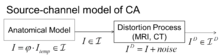

The random orbit model of computational anatomy

The random orbit model of computational anatomy first appeared in[128][129][130] modelling the change in coordinates associated to the randomness of the group acting on the templates, which induces the randomness on the source of images in the anatomical orbit of shapes and forms and resulting observations through the medical imaging devices. Such a random orbit model in which randomness on the group induces randomness on the images was examined for the Special Euclidean Group for object recognition in.[131]

The random orbit model induces the prior on shapes and images conditioned on a particular atlas . For this the generative model generates the mean field as a random change in coordinates of the template according to , where the diffeomorphic change in coordinates is generated randomly via the geodesic flows. The prior on random transformations on is induced by the flow , with constructed as a Gaussian random field prior . The density on the random observables at the output of the sensor are given by

The central statistical model of computational anatomy in the context of medical imaging has been the source-channel model of Shannon theory;[128][129][130] the source is the deformable template of images , the channel outputs are the imaging sensors with observables (see Figure).